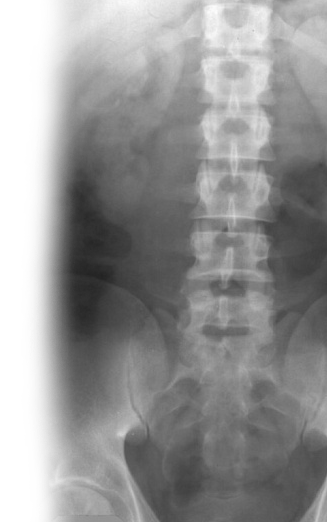

Рентгенография почек и мочевыводящих путей – важный метод визуализации почек, мочеточников и мочевого пузыря.

С помощью рентгенографии определяется положение почек, определяется наличие камней в мочевыделительной системе.

Внутривенная урография - метод диагностики аномалий строения почек и мочевыводящих путей, опухолей, кист, камней; оценки выделительная функция почек.